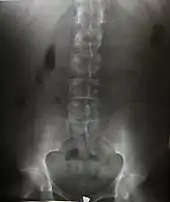

Radiography is an imaging technique using X-rays, gamma rays, or similar ionizing radiation and non-ionizing radiation to view the internal form of an object. Applications of radiography include medical ("diagnostic" radiography and "therapeutic") and industrial radiography. Similar techniques are used in airport security, (where "body scanners" generally use backscatter X-ray). To create an image in conventional radiography, a beam of X-rays is produced by an X-ray generator and it is projected towards the object. A certain amount of the X-rays or other radiation are absorbed by the object, dependent on the object's density and structural composition. The X-rays that pass through the object are captured behind the object by a detector (either photographic film or a digital detector). The generation of flat two-dimensional images by this technique is called projectional radiography. In computed tomography (CT scanning), an X-ray source and its associated detectors rotate around the subject, which itself moves through the conical X-ray beam produced. Any given point within the subject is crossed from many directions by many different beams at different times. Information regarding the attenuation of these beams is collated and subjected to computation to generate two-dimensional images on three planes (axial, coronal, and sagittal) which can be further processed to produce a three-dimensional image.

Since the body is made up of various substances with differing densities, ionising and non-ionising radiation can be used to reveal the internal structure of the body on an image receptor by highlighting these differences using attenuation, or in the case of ionising radiation, the absorption of X-ray photons by the denser substances (like calcium-rich bones). The discipline involving the study of anatomy through the use of radiographic images is known as radiographic anatomy. Medical radiography acquisition is generally carried out by radiographers, while image analysis is generally done by radiologists. Some radiographers also specialise in image interpretation. Medical radiography includes a range of modalities producing many different types of image, each of which has a different clinical application.

The creation of images by exposing an object to X-rays or other high-energy forms of electromagnetic radiation and capturing the resulting remnant beam (or "shadow") as a latent image is known as "projection radiography". The "shadow" may be converted to light using a fluorescent screen, which is then captured on photographic film, it may be captured by a phosphor screen to be "read" later by a laser (CR), or it may directly activate a matrix of solid-state detectors (DR—similar to a very large version of a CCD in a digital camera). Bone and some organs (such as lungs) especially lend themselves to projection radiography. It is a relatively low-cost investigation with a high diagnostic yield. The difference between soft and hard body parts stems mostly from the fact that carbon has a very low X-ray cross section compared to calcium.